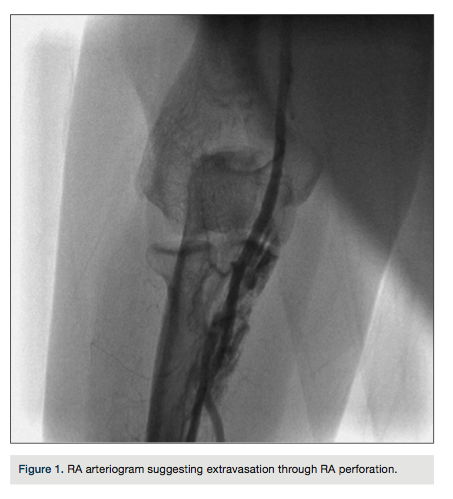

The right radial artery (RA) was utilized for access. After injecting intradermal local anesthesia,

the RA was punctured with a 21-gauge needle, a 0.018” guidewire was introduced, and a 10-centimeter (cm), 6-French (Fr) hydrophilic-coated sheath was placed. Resistance was felt on advancement of the 0.035-inch J-tip wire through the sheath at the proximal forearm level. While advancing a 0.035-inch hydrophilic steerable wire, an iatrogenic perforation occurred and was confirmed by radial arteriography (Figure 1). The following technique was used to treat the perforation.